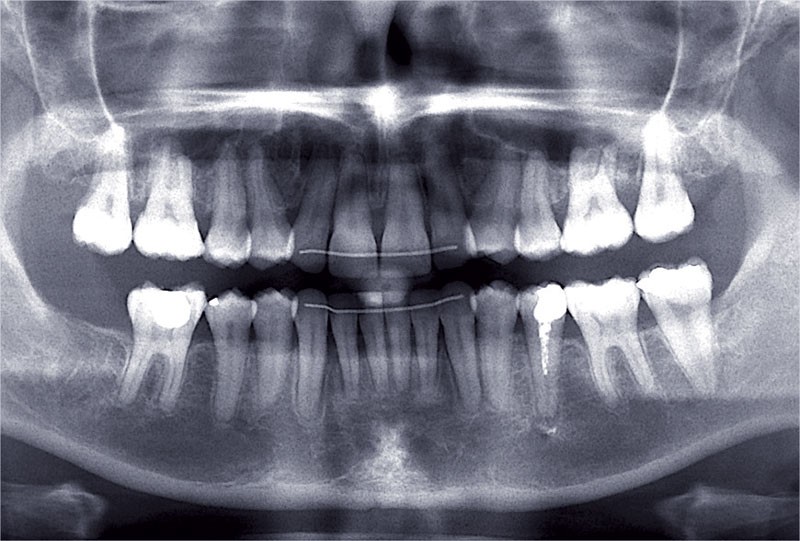

Nous lui avons donc proposé un traitement d’alignement avec maintien des 14 et 24 en position de 13 et 23 et optimisation du torque pour favoriser un développement des arcades et chercher à améliorer le sourire et le soutien labial.

Un appareillage Damon métal a été mis en place, réalisé à partir d’un set up numérique Insignia pour obtenir un contrôle précis des torques et de la forme d’arcade et réduire le temps de finition grâce à un collage indirect très précis.

De larges surélévations postérieures étalées ont été mises en place et la patiente a porté des élastiques précoces suivant les principes de la technique Damon. Les 14 et 24 rempliront le rôle des 13 et 23.

Les objectifs de traitement ont été remplis. Nous avons observé un excellent contrôle du torque et une absence de perte de l’occlusion postérieure grâce à la technique Insignia.